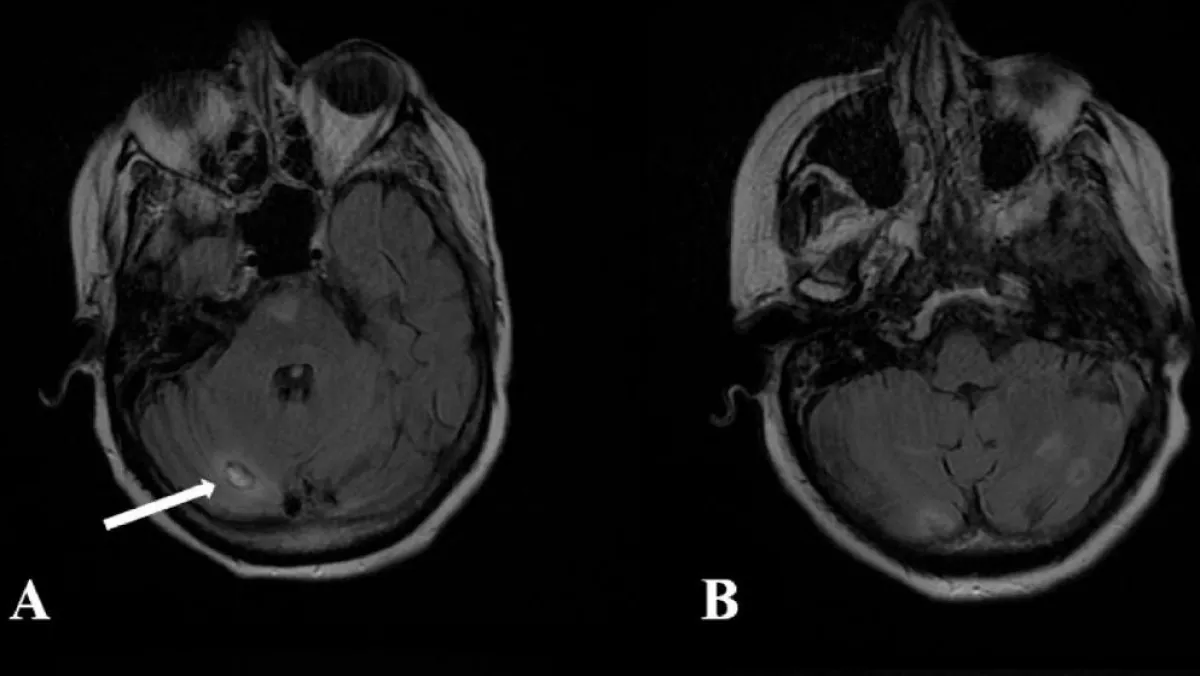

Egy év alatt sem múlt el a méretes folt, majd váratlanul a nőnek rohama lett, kórházba került. A CT-vizsgálatok a fejében azonnal kimutattak egy másfél centiméteres foltot, az orvosok azt gondolták, daganat.